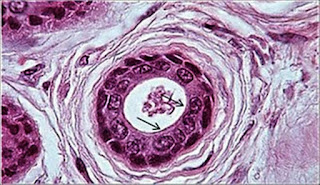

EPITELIO CUBICO SIMPLE-Este epitelio esta conformado por una única capa

de células poligonales igual de altas que anchas, con un núcleo de

ubicación central y redondo, Las células aparecen cuboidales en cortes

perpendiculares a la superficie del epitelio. Vistas desde la superficie

del epitelio lucen mas bien como pequeños polígonos. Los epitelios

cubicos simples existen en los conductos excretores pequeños de muchas

glándulas, los folículos de la glándula tiroides, los túbulos del riñón y

en la superficie de los ovarios.

El epitelio cúbico simple está formado por células que presentan un

núcleo situado central o ligeramente basal y esférico. Tapiza

superficies de secreción (glándula tiroides), de conducción (conductos

de glándulas exocrinas), de protección (superficie del ovario) y de

absorción/excreción (túbulos renales).